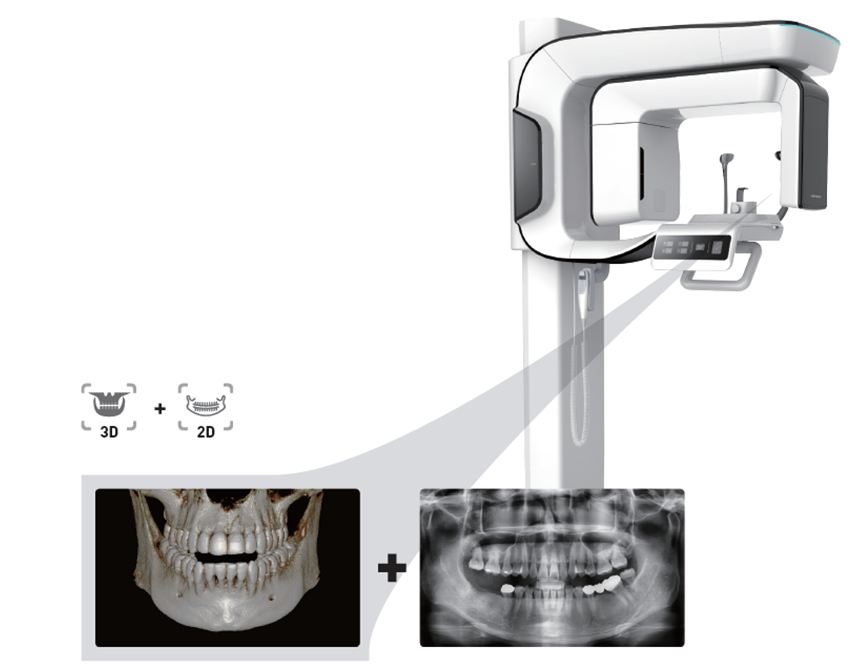

ONE SCAN, TWO IMAGES One scan with a i3D Smart gives you not just a CT image but also an Auto Pano image. This means, patients who require both images do not need to undergo two X-ray scans. Also, CT and Auto Pano images are displayed within the One Viewer feature.

2D and 3D in One Viewer

Viewing 2D and 3D images together provides many benefits. There is no need to utilize two different software programs and the One Viewer feature presents a professional look for your patients. This layout helps patients better understand the images, which will eventually result in increasing acceptance rates.